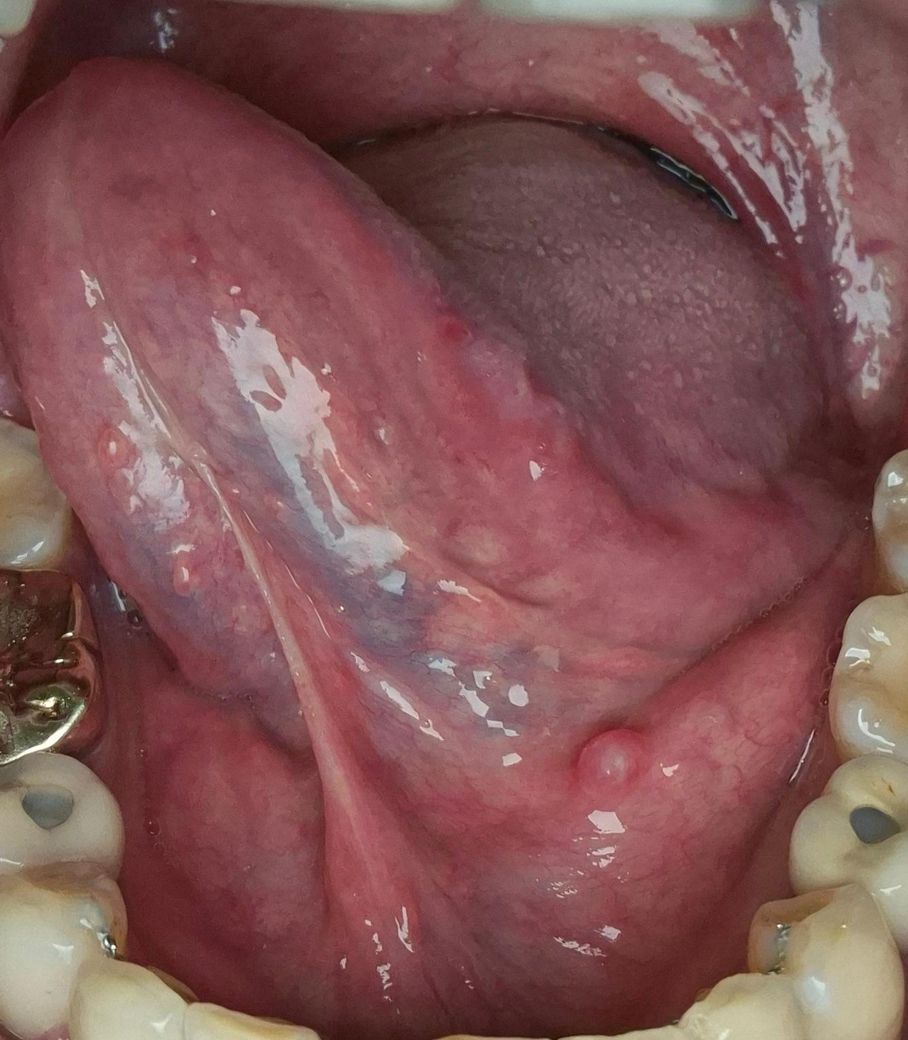

• 2번 째 사진

• 사진상 설하부(혀 밑) 점막에 2–3 mm 정도의 둥근 융기 병변이 보이며, 표면은 비교적 매끈하고 반투명 또는 약간 창백한 색조로 관찰됩니다. 통증이 없고 이물감만 있는 점을 고려하면 다음 가능성이 우선입니다.

가장 흔한 것은 점액낭종입니다. 소타액선(설하선 또는 하악설하선)에서 분비되는 점액이 배출되지 못하고 고여 생기는 병변으로, 설하부에 비교적 흔합니다. 크기가 작고 통증이 없는 경우가 많으며, 시간이 지나면서 커졌다 작아졌다 하거나 자연 소실되기도 합니다.

감별로는 소타액선 관 폐쇄(침샘관 막힘) 또는 초기 타석증 가능성도 있습니다. 다만 타석은 보통 식사 시 통증이나 부종이 동반되는 경우가 많아 현재 양상과는 다소 거리가 있습니다. 그 외 드물게는 섬유종, 유두종 같은 양성 종양도 가능하지만, 사진상 전형성은 점액낭종 쪽이 더 높습니다.

진료는 치과 구강외과 또는 이비인후과 모두 가능하나, 구강 점막 및 타액선 질환은 치과 구강외과가 더 직접적인 평가가 가능합니다. 필요 시 초음파 또는 단순 촉진으로 관 폐쇄 여부를 확인하고, 지속되거나 커질 경우 국소마취 하 절제 또는 개창술을 시행합니다.